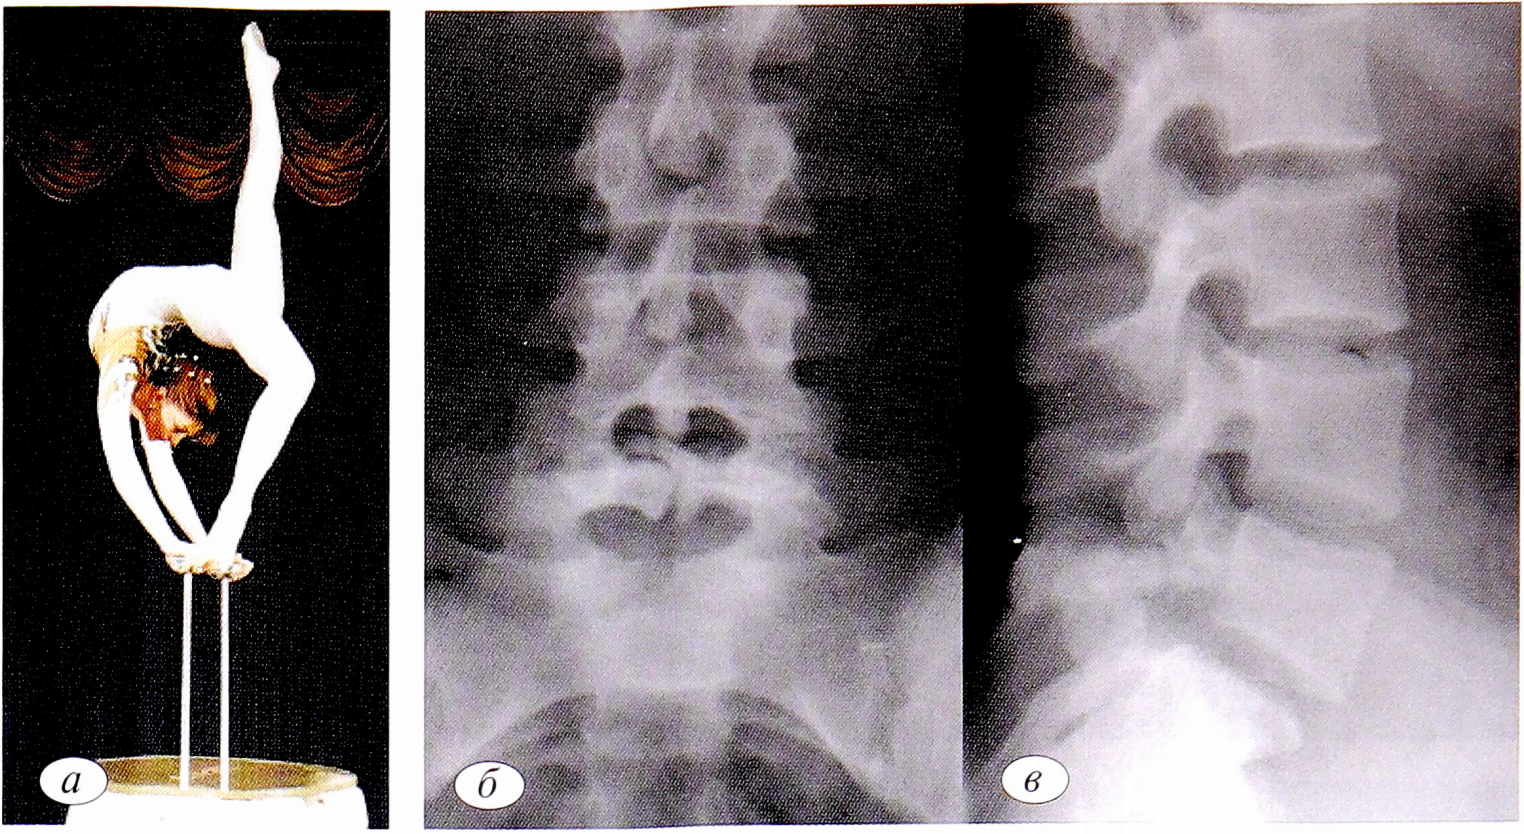

Следующий клинический случай демонстрирует постепенное развитие перестроечного процесса в дужке позвонка и прогрессирование нестабильности в результате значительных нагрузок.

Пациентка П., заслуженный мастер спорта по спортивной гимнастике, член сборной России. Впервые боли в поясничном отделе появились в 2010 г. на фоне интенсивных тренировок. На рентгенограммах обнаружен переходный пояснично-крестцовый позвонок, spina bifida S,. Клинический диагноз, подтвержденный данными ультрасонографии: микроповреждения длиннейшей мышцы поясницы, подвздошно- поясничной и крестцово-подвздошной связок слева (рис. 4, а—в). Через 1 год в 2011 г. обследована по поводу рецидива болевого синдрома. На рентгенограммах выявлены спондилолиз позвонка Lv, нестабильность Lv—S1 (рис. 4, г—е). На магнитно-резонансных томограммах определялись протрузии дисков LIII-LIV (3,2 мм), LIV-LV (5,2 мм), Lv-SI (4,2 мм). Как следствие развившейся нестабильности — миофасциальный болевой синдром задней группы мышц обоих бедер, тендопериостеопатия седалищных бугров. В 2015 г. отмечены прогрессирование нестабильности Lv— SI, антелистез позвонка Lv. По данным магнитно-резонансной томографии (МРТ) определялись протрузии дисков LIII-LIV (3,5 мм), L1V— Lv (4,5 мм), Lv—SI (6,5 мм) (рис. 4, ж—и). Несмотря на прогрессирование нестабильности, спортсменка успешно выступила на Олимпиаде в 2016 г., завоевав серебряную медаль.

Рис. 4. Больная 77., заслуженный мастер спорта, спортивная гимнастика, сборная России (a). Рентгенограммы поясничного отдела позвоночника: б, в — 2010 г: spina bifida SI, другой костной патологии не обнаружено; г—е — 2011 г.: спондилолиз позвонка Lv, нестабильность Lv—SI; ж—и — 2015 г.: спондилолизный спондилолистез позвонка Lv, прогрессирование нестабильности LV—SI.

Fig. 4. Patient P., honored master of sports, gymnastics, Russian national team (a). Radiographs of the lumbar spine: b, c — 2010 g: spina bifida SI, no other bone pathology was found; g — e — 2011: Lv vertebra spondylolysis, LV-SI instability; g—i — 2015 g: LV vertebra spondylolisthesis, LV-SI instability progression.